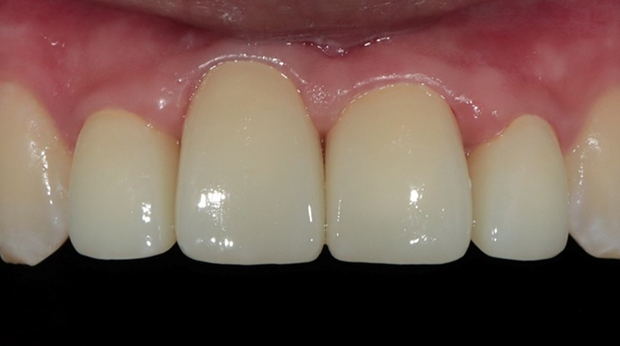

라미네이트

치과 공포증을 해소하여 적절한 치료시기를 놓치지 마세요!

자면서 치료받는, 의식하진정법(수면진정치료)

자고 일어나면, 모든 치료가 끝나 있습니다.

시술 시간도 빠르기 때문에 마취가 풀려도 통증과 붓기가 거의 없습니다.